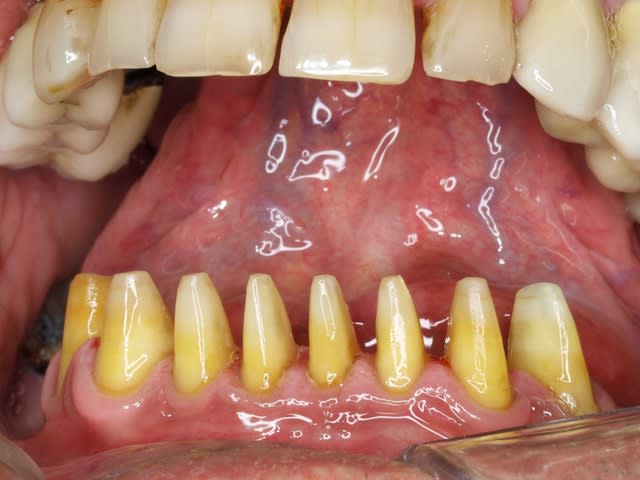

Pour tous ceux qui ont trouvé l'empreinte postée plus haut jolie, et qui ne savent visiblement pas ce qu'est une belle empreinte... je me suis senti obligé de faire la 1ère photo de mon travail ; eh oui, il y en a qui parle sur le forum, et d'autres qui bossent... :-)

Donc, dernière empreinte de la journée, prise à 19h20 en deux temps, avec du flexitime à prise rapide.

Bref, désolé pour la qualité, la photo a été prise avec mon smartphone. Je n'ai pas encore pris le temps d'utiliser mon reflex acheté il y a plus de 9 mois...